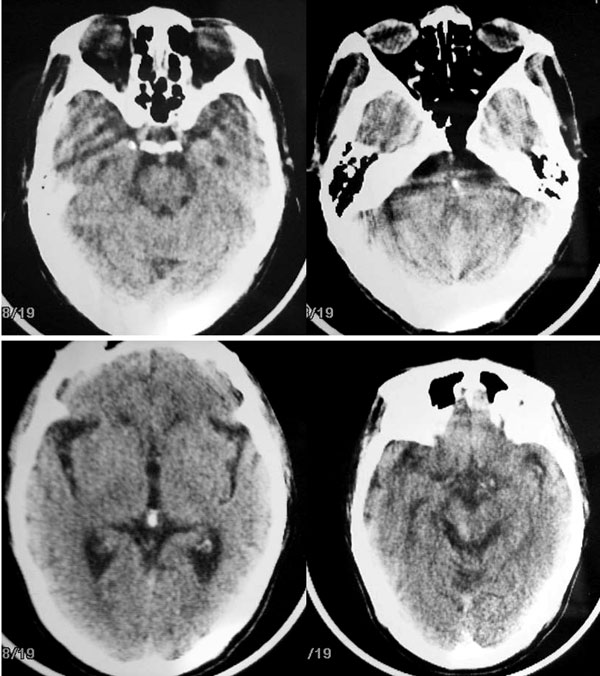

以下是引用卜一在2006-11-11 18:14:00的发言:[br]多发性腔梗,脑白质脱髓鞘变性,脑萎缩(老年性脑内三联征),考虑:皮层下动脉硬化性脑病.